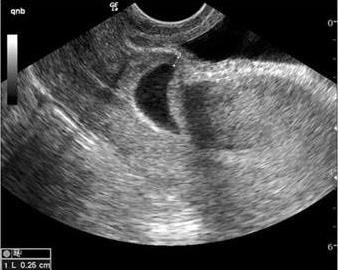

Hình 1.3. Hình ảnh BTC và ống CTC rỗng, túi thai làm tổ tại cơ tử cung mặt trước [20]

Siêu âm đường âm đạo chẩn đoán chửa SMLT có độ nhạy 84,6% [23]. Việc kết hợp với siêu âm đường thành bụng khi bàng quang đủ nước tiểu giúp

nhận định một góc độ khác của hình ảnh tử cung, phần phụ và đánh giá được độ dày của cơ tử cung giữa bàng quang và túi ối [22]. Độ mỏng của lớp cơ tử cung giữa túi ối và bàng quang dưới 5mm được ghi nhận trong 2/3 số trường hợp chửa SMLT. Sự mỏng hay mất lớp cơ vị trí này giải thích hiện tượng vỡ tử cung ở một vài trường hợp chửa SMLT [3,6]. Theo Timor - Tritsch, phương tiện chẩn đoán tốt nhất là siêu âm đường âm đạo có tần số cao [3]. Tuy nhiên siêu âm đường thành bụng và chụp cộng hưởng từ cũng được đề cập như những phương tiên hỗ trợ thêm cho chẩn đoán.